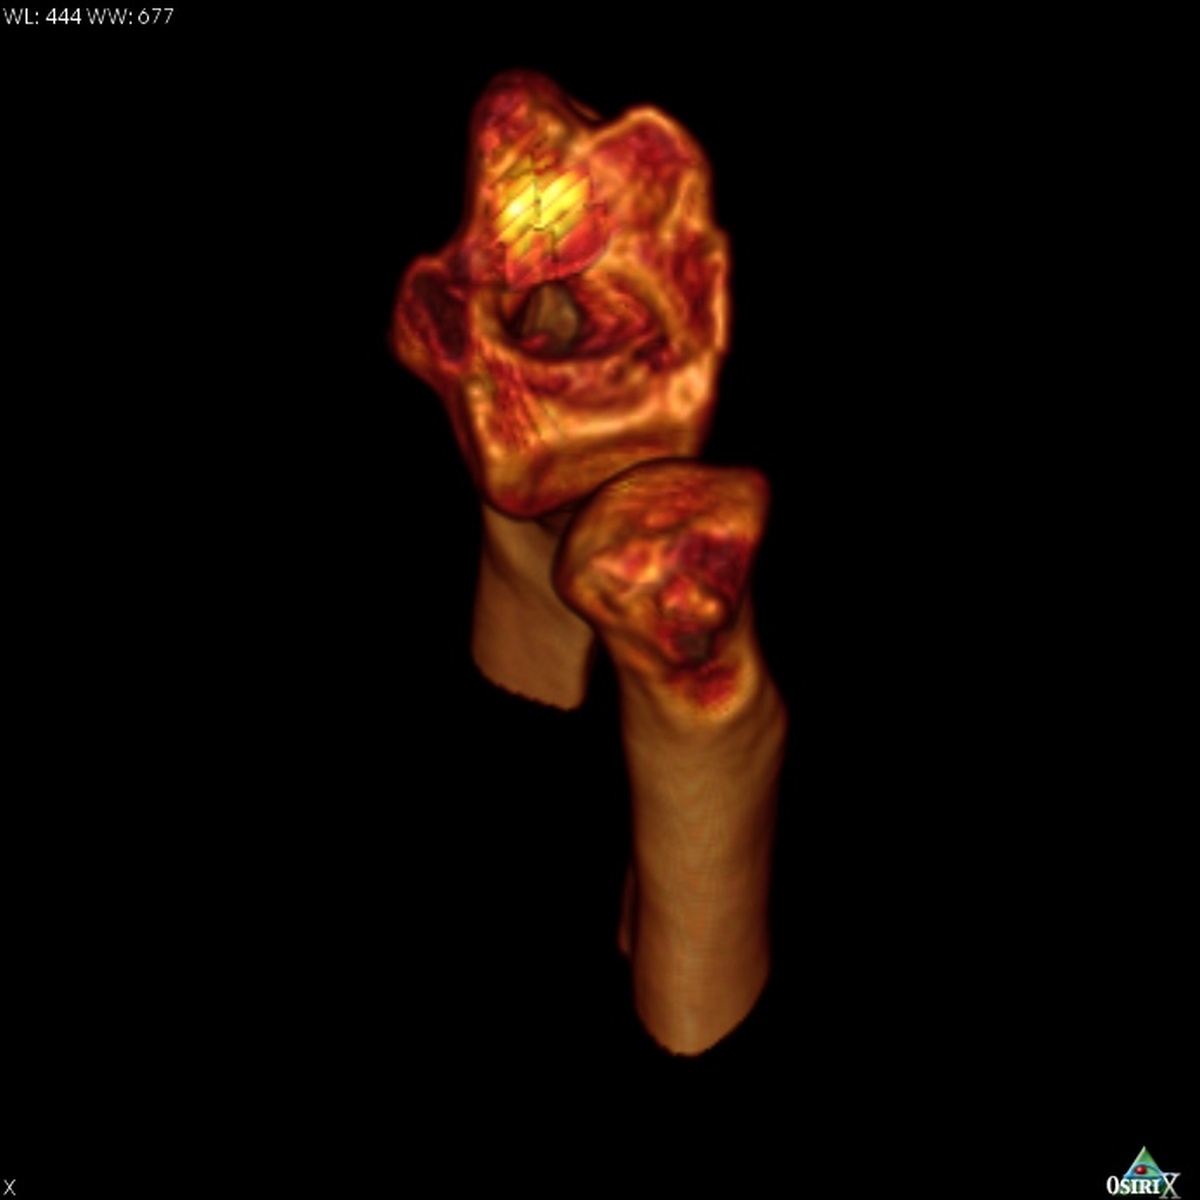

| On first glance, 3D CT

reconstruction looked favorable for possible simple dorsal opening

wedge corrective osteotomy. |

| Digitally hiding the carpal bones obstructing the view of the distal radius shows a much more significant articular defect. In these views, the

proximal cortex of the scaphoid remains as a yellowish shell - it could not be cleanly

removed because it is in bony contact with the dordal lip of the radius. |